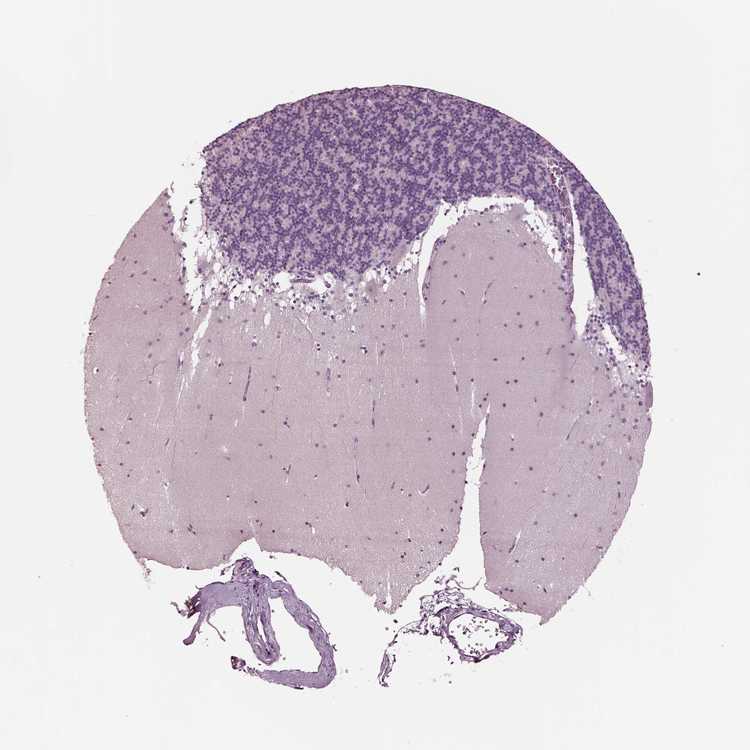

CEREBELLUM - Antibody stainingi

Antibody staining in the annotated cell types in the current human tissue is reported as not detected, low, medium, or high, based on conventional immunohistochemistry profiling in selected tissues. This score is based on the combination of the staining intensity and fraction of stained cells.

Each image is clickable and will lead to virtual microscopy that enables deeper exploration of all samples and also displays staining intensity scores, fraction scores and subcellular localization as well as patient and tissue information for each sample.

Antibody HPA068322

Purkinje cells Not detected

Cells in granular layer Not detected

Cells in molecular layer Not detected